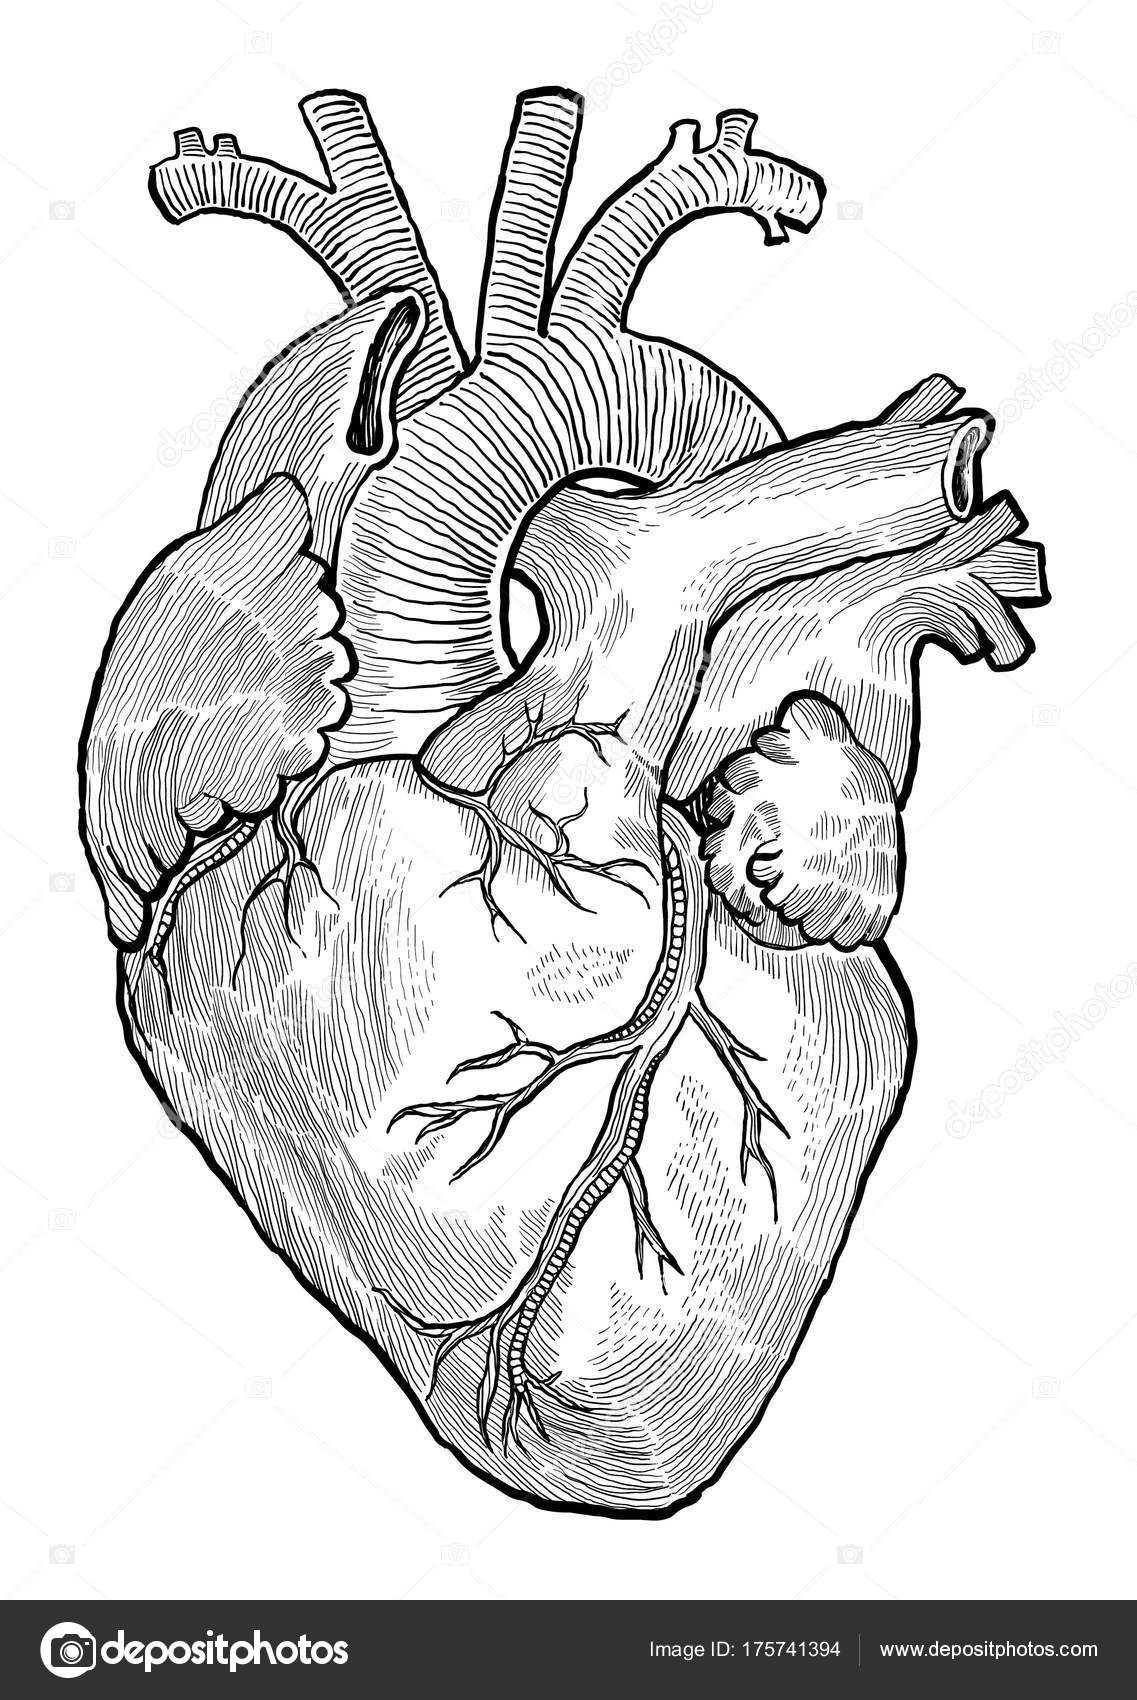

Gross Anatomy Of The Human Heart Digital Art by Stocktrek Images  Human Heart Drawing by Granger - Fine Art America

Human Heart Drawing by Granger - Fine Art America  Human Heart Anatomy Drawing at GetDrawings | Free download

Human Heart Drawing line work vector image on VectorStock | Human heart drawing, Heart drawing  Drawing Internal Structure Human Heart Images - anonimamentemivida

Drawings: human heart in pencil | Human Heart Sketch Stock Illustration â Stock Vector  human body heat loss (With images) | Human heart diagram, Human anatomy picture, Human heart anatomy

Human Heart Drawing Line Work stock vector art 481404348 | iStock  Human Heart 3D model realtime | CGTrader